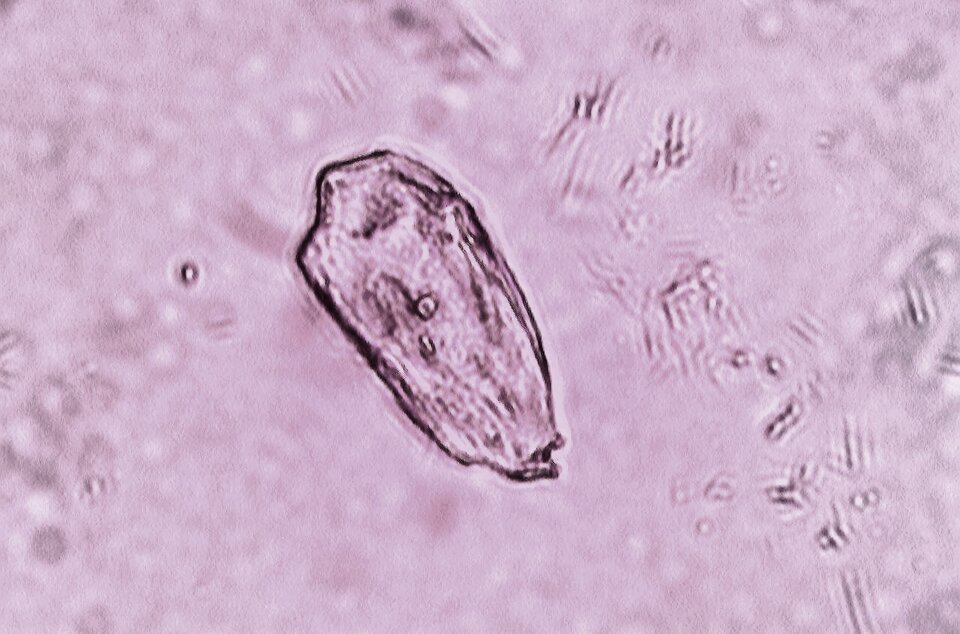

Osad jest oceniany mikroskopowo pod względem obecności w nim takich elementów, jak: erytrocyty, leukocyty, komórki nabłonkowe, kryształy oraz bakterie.

Kryształy | nie stwierdza się | obecne – kamica nerkowa (kryształy szczawianu wapnia) |